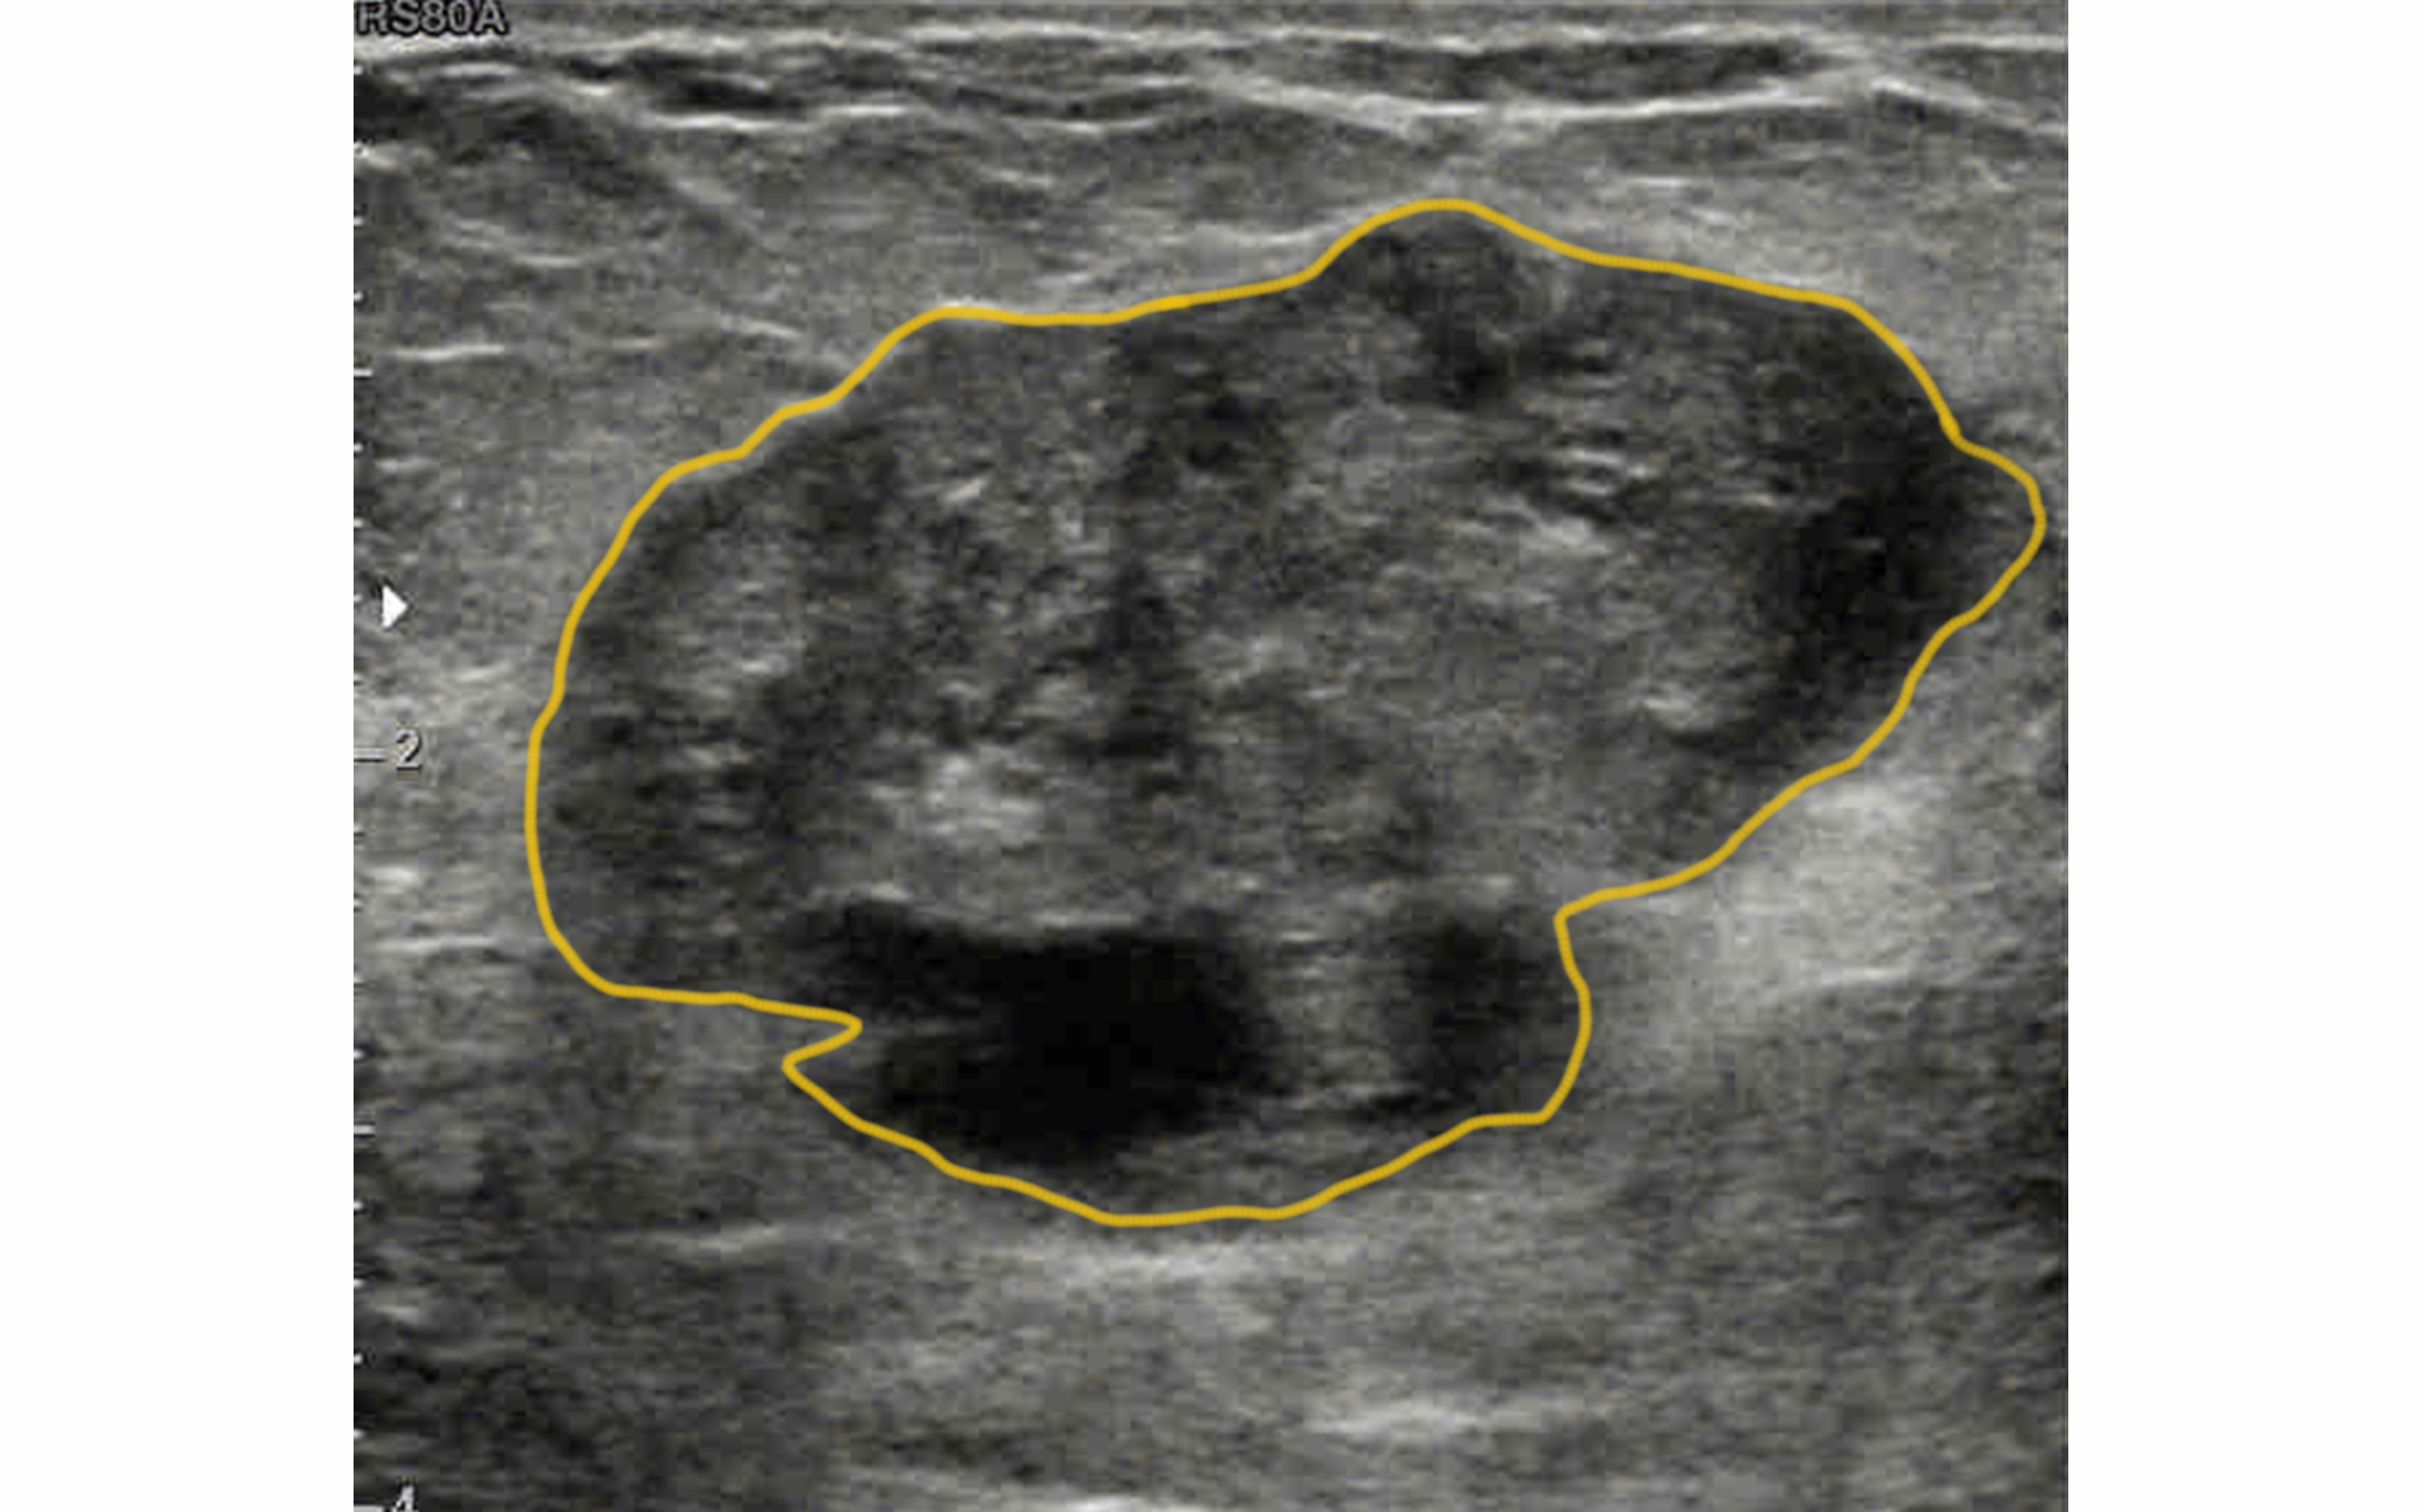

GroundTruth

Case-167-G1

Malignant Solid Mass